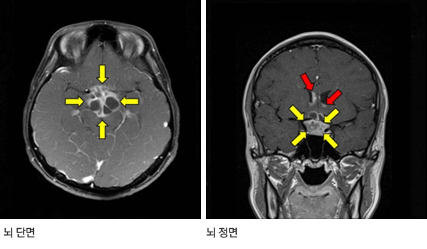

뇌 자기공명영상(MRI)이나 컴퓨터 단층촬영(CT)을 통해 송과체(멜라토닌이라는 호르몬을 분비하는 뇌 후부에 위치한 기관)나 뇌하수체 등에 종양의 유무를 확인한다. 자기공명영상(MRI)이나 컴퓨터 단층촬영(CT) 시 조영제를 투여하면 종양의 특징과 주변 부위로의 파급여부를 파악하는 데 큰 도움이 된다. 양전자 단층촬영(Positron emission tomography, PET)을 시행하여 같은 부위에 발생하는 다른 종양과 감별진단을 하기도 한다.

뇌하수체에 종양이 발생할 경우 다갈증, 다뇨, 야뇨 등이 나타나는 요붕증이 발생할 수 있으며, 성장호르몬 장애로 인한 발육장애가 나타나기도 한다. 융모막 암종의 경우 종양에서의 호르몬 분비로 2차 성징이 비정상적으로 빠르게 나타날 수 있다.

뇌하수체에 발생한 종양이 시신경이나 시신경 교차를 압박하여 시력 감소, 시야 결손이 발생할 수 있다.